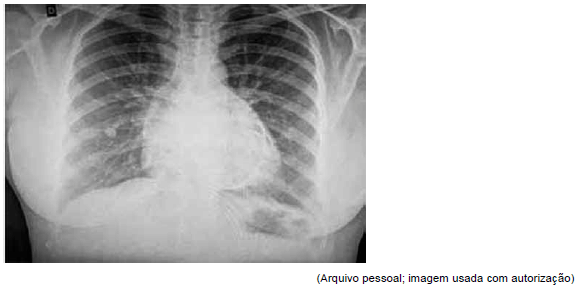

Mulher, 48 anos, procura o pronto atendimento com queixa de dor torácica retroesternal há 1 semana, do tipo pontada, sem irradiação e de caráter progressivo e contínuo, evoluindo com dispneia aos esforços há 2 dias. Não refere antecedentes relevantes e não faz uso de medicações contínuas. Foi realizada a radiografia de tórax, ilustrada a seguir:

Na investigação dessa paciente, a alteração ecocardiográfica que se espera encontrar é: